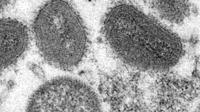

(CNN) - Six people who tested positive for monkeypox - two in New York City, two in Chicago, one in Nevada and one in Maryland - have died, local health departments have confirmed.

New monkeypox cases in the United States have been steadily dropping in recent weeks but concern remains about the possibility of severe illness or death, especially in immunocompromised people.

There were 27,884 probable or confirmed monkeypox cases reported in the US as of Friday, according to the Centers for Disease Control and Prevention.